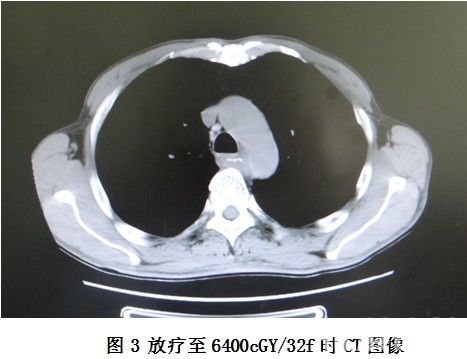

放疗6次时,患者体温逐渐下降,9次时发热症状消失,进食哽咽症状有所缓解。放疗至20次时复查食管CT(见图2)与放疗前定位CT片(见图1)比较,肿瘤明显缩小。放疗至DT6600cGY/33f时,进食哽咽症状明显缓解,复查食管CT(图3),见肿瘤进一步缩小。期间复查肝、胆、胰、脾、腹腔淋巴结、浅表淋巴结彩超未见明显异常。